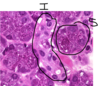

Eccrine sweat gland of Thick skin with resorptive duct and secretory coil – 2 profiles: darker stained is duct portion (modifies secretions), lighter stained is secretory portion (secretes components of sweat: proteins, electrolytes, ammonia, urea). Darker stained duct portion has STRATIFIED CUBOIDAL epithelium with lumen (2 layers of cells). Lighter stained secretory portion has PSEUDOSTRATIFIED EPITHELIUM around the gland and also a ring of darker eosinophilic cells called MYOEPITHELIAL cells on the outside.